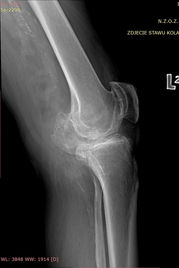

CHIRURGIA KOLANA

Bardzo często przyjmuję w gabinecie pacjentów cierpiących z powodu problemów ze stawem kolanowym. Szczegółowe badanie, znajomość anatomii i złożonej mechaniki kolana pozwala mi trafnie dobierać leczenie dzięki czemu pacjenci szybko wracają do zdrowia i aktywności sportowej, a także unikają powikłań w przyszłości.